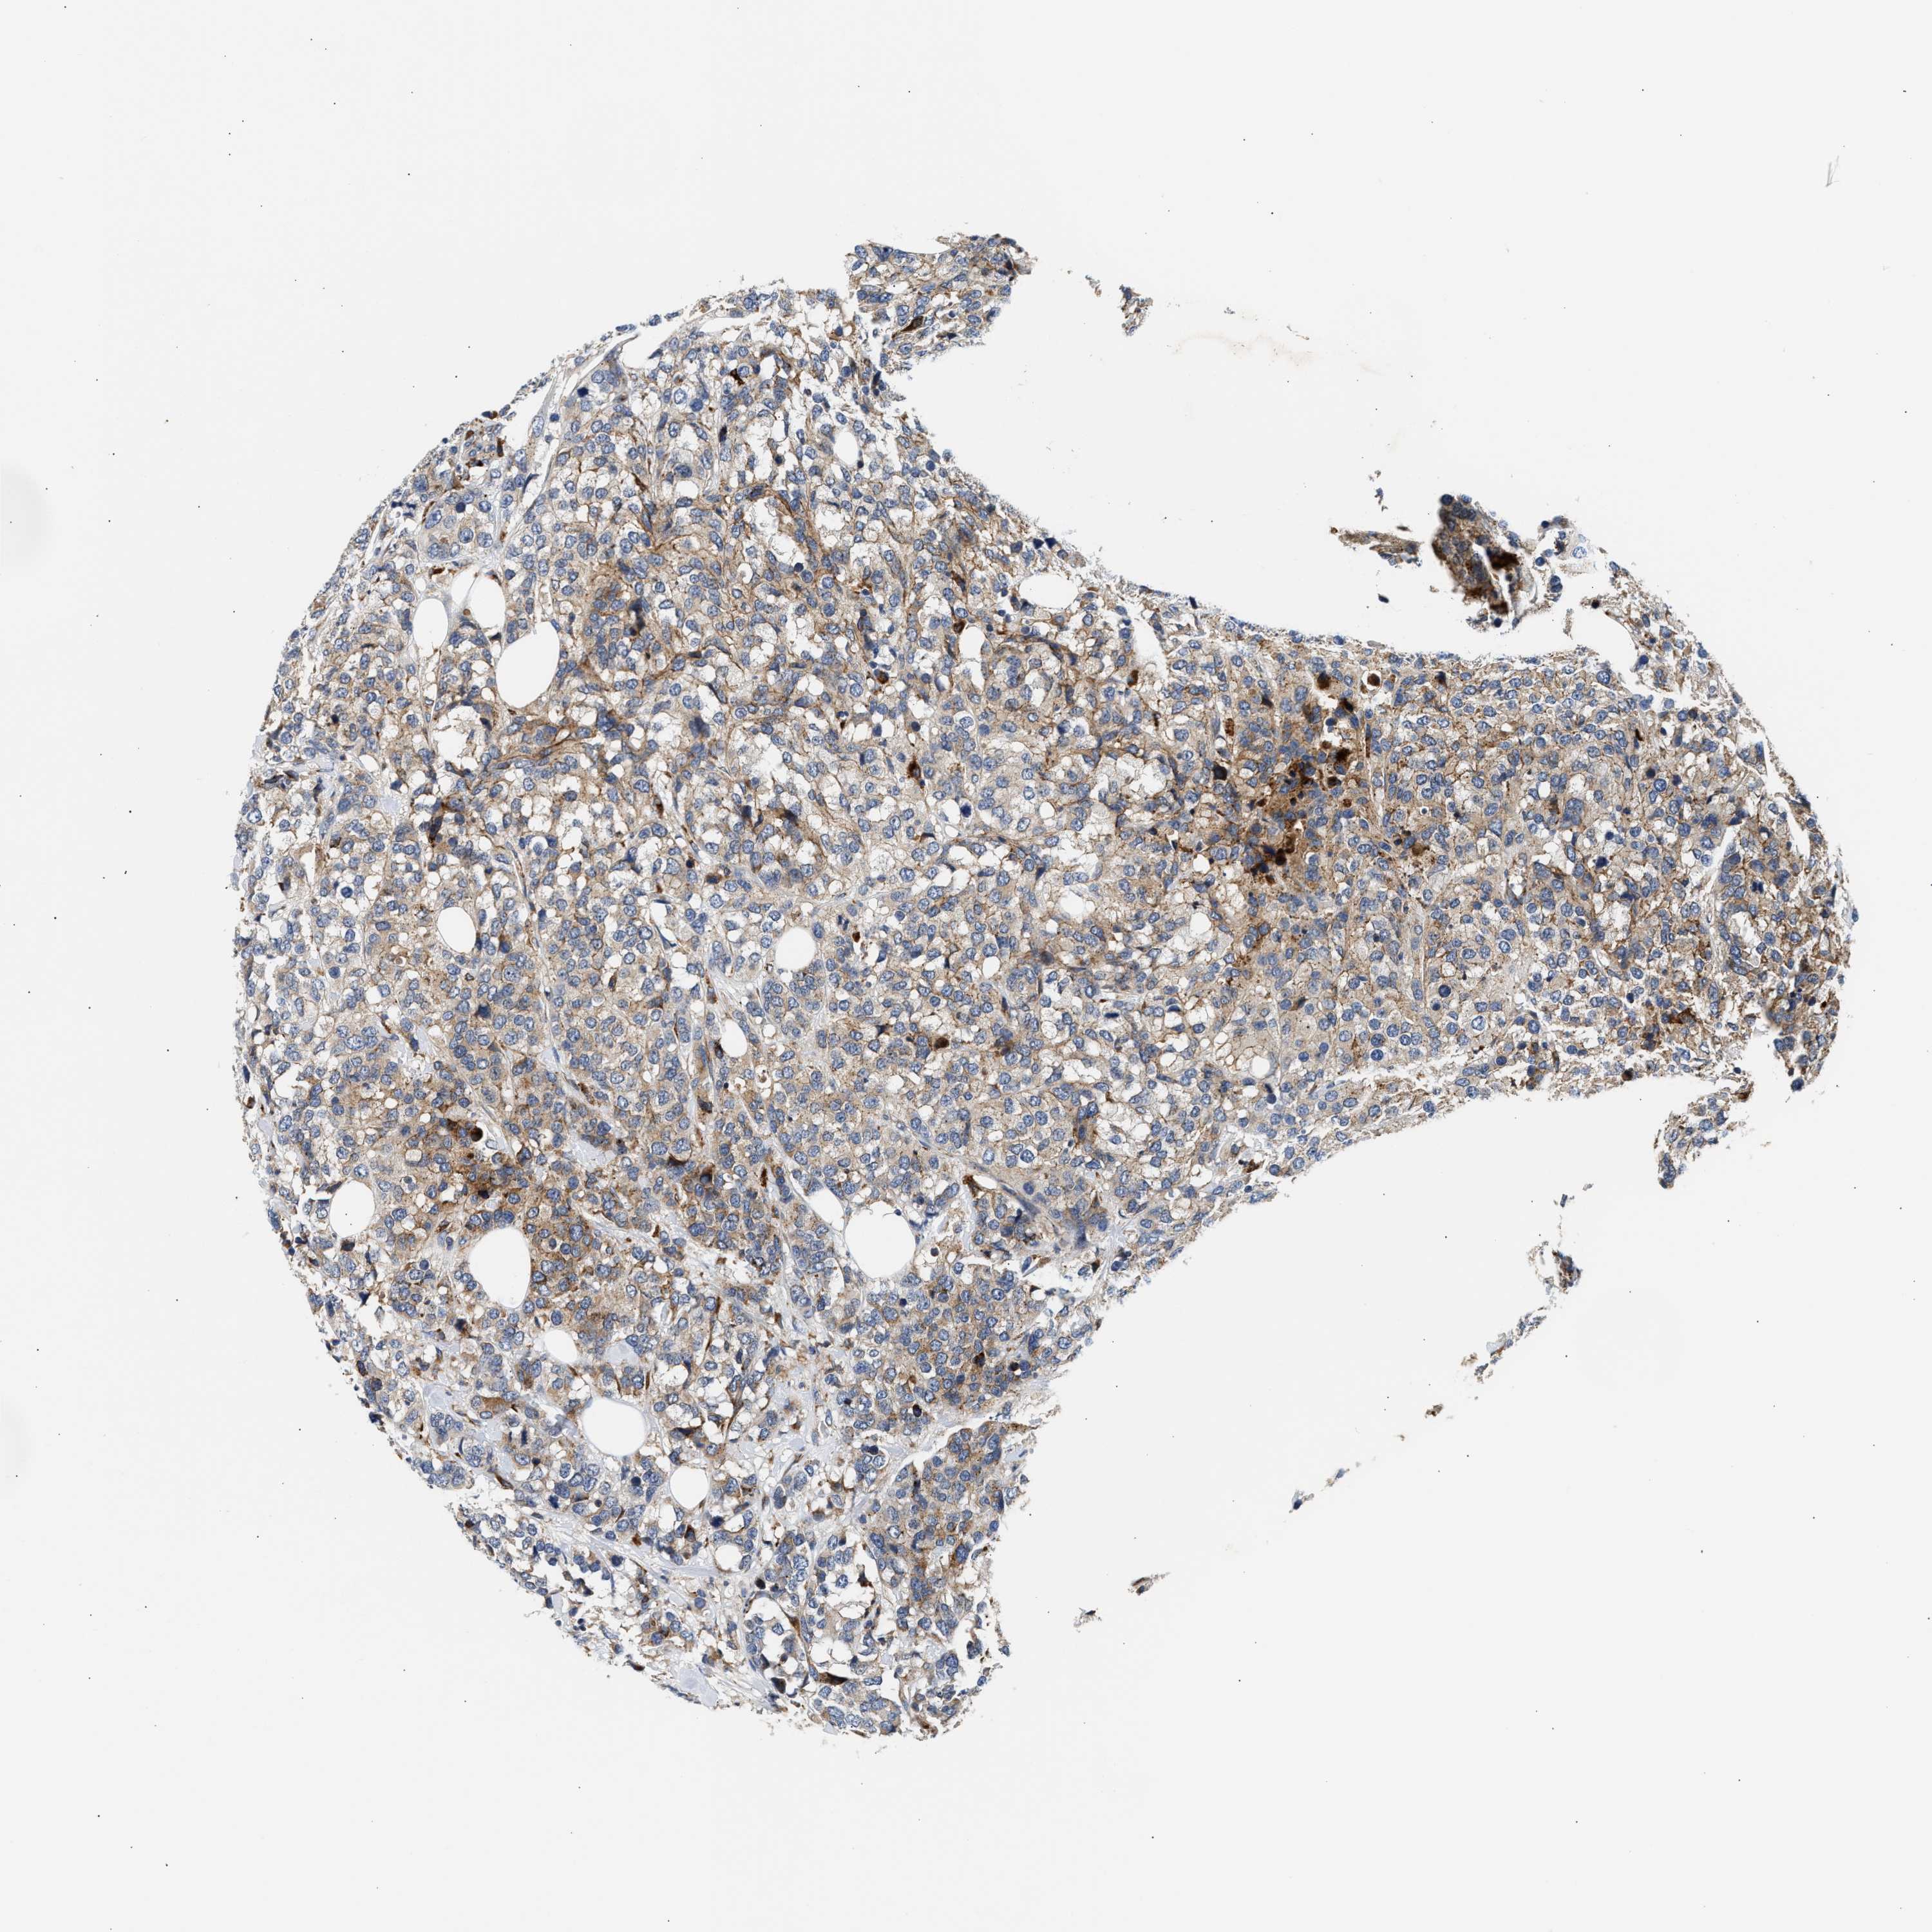

CANCER BREAST CANCER Show tissue menu

BRCA TCGA BRCA VALIDATION PROTEIN EXPRESSION

ANTIBODIES

AND

VALIDATION